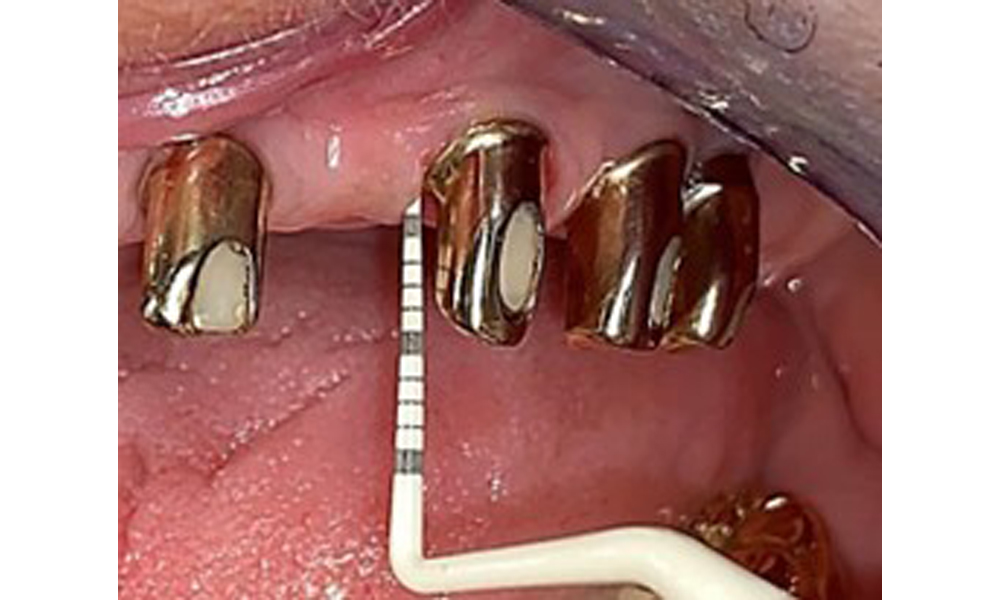

The patient was fitted with a combined removable maxillary telescopic prosthesis more than 25 years ago (Fig. 1, Fig. 2, Fig. 3) and is very happy with her dentures. The patient has an adequate fixed denture for the mandible (Fig. 4).

The dental findings are as follows: Combined removable implant and tooth-supported telescopic prostheses on implants 15, 13, 21, 23, 24, 25 and tooth 11 (Fig. 1, Fig. 2, Fig. 3). The patient was fitted with a fixed mandibular denture. Adequate bridges were present over 37 to 34 and 45 to 47 (Fig. 4), the crown margins were intact and there were no active caries. A composite filling with a marginal gap was present on tooth 43. There was mandibular gingival recession, exposing 1 to 3 mm of root surface. This also applies to 11.

Occlusal view: Maxilla with tooth and implant-supported telescopic prostheses.

Fig. 2: Occlusal view: Maxilla with tooth and implant-supported telescopic prostheses